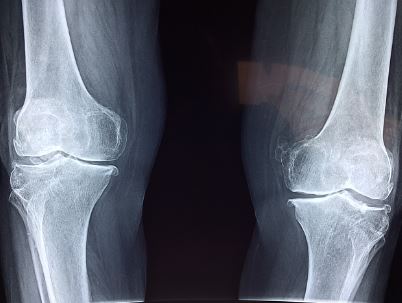

나이가 들어가면 무릎 연골이 닿아서 통증을 달고 사는 아버지, 어머니 그리고 어르신들이 많이 있습니다. 인공 관절 수술을 비용이 많이 들어가는 수술이기 때문에 많은 분들이 고민을 많이 하시는데, 무릎 인공 관절 수술 비용 지원 사업 신청 대상 및 방법에 대해서 소개하도록 하겠습니다.

고질적인 무릎 통증에 시달리며, 경제적으로 여유가 없어 수술을 받지 못하는 분들에게 고통을 경감하고 삶의 질 개선하고 노인 건강 보장 및 의료비 부담 경감이 목적인 복지 정책입니다.

무릎 인공 관절 수술 비용 지원 사업은 경제적으로 어려움을 겪고 있는 노인분들이 대상이며 아래 항목이 만족해야 합니다.

- 건강보험급여 '인공관절치환술 (슬관절)' 인정 기준에 준하는 환자